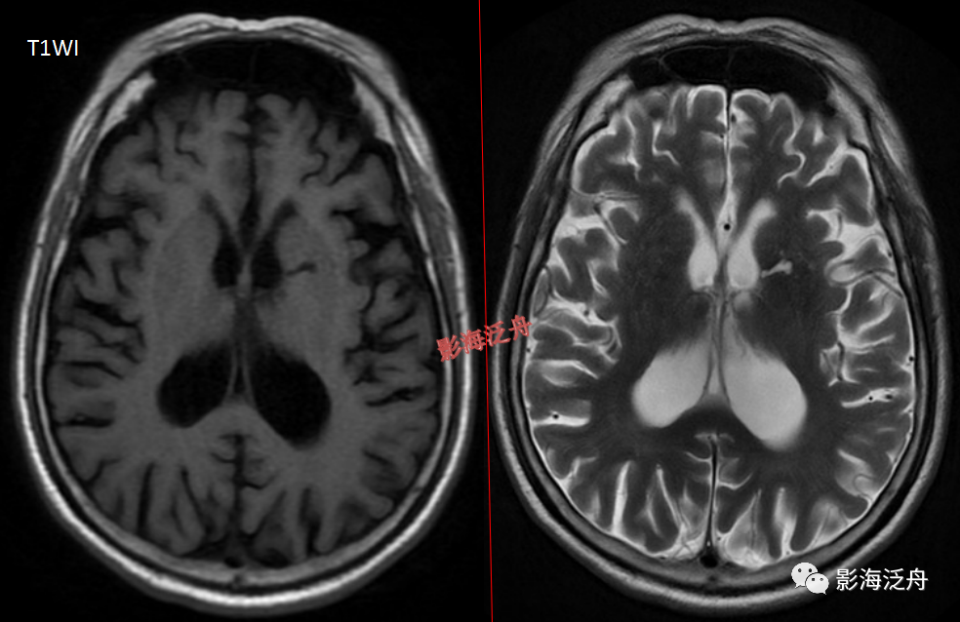

病例一:青少年男性,头痛就诊。右侧大脑半球多发扩大VR腔隙,病灶沿髓质动脉走行区域(红箭)呈簇状分布,VR腔隙呈类圆形或类椭圆形,边缘光滑,灶周不伴水肿。大脑半球型扩大VR腔隙多两侧不对称,这与基底节型不同。

图片